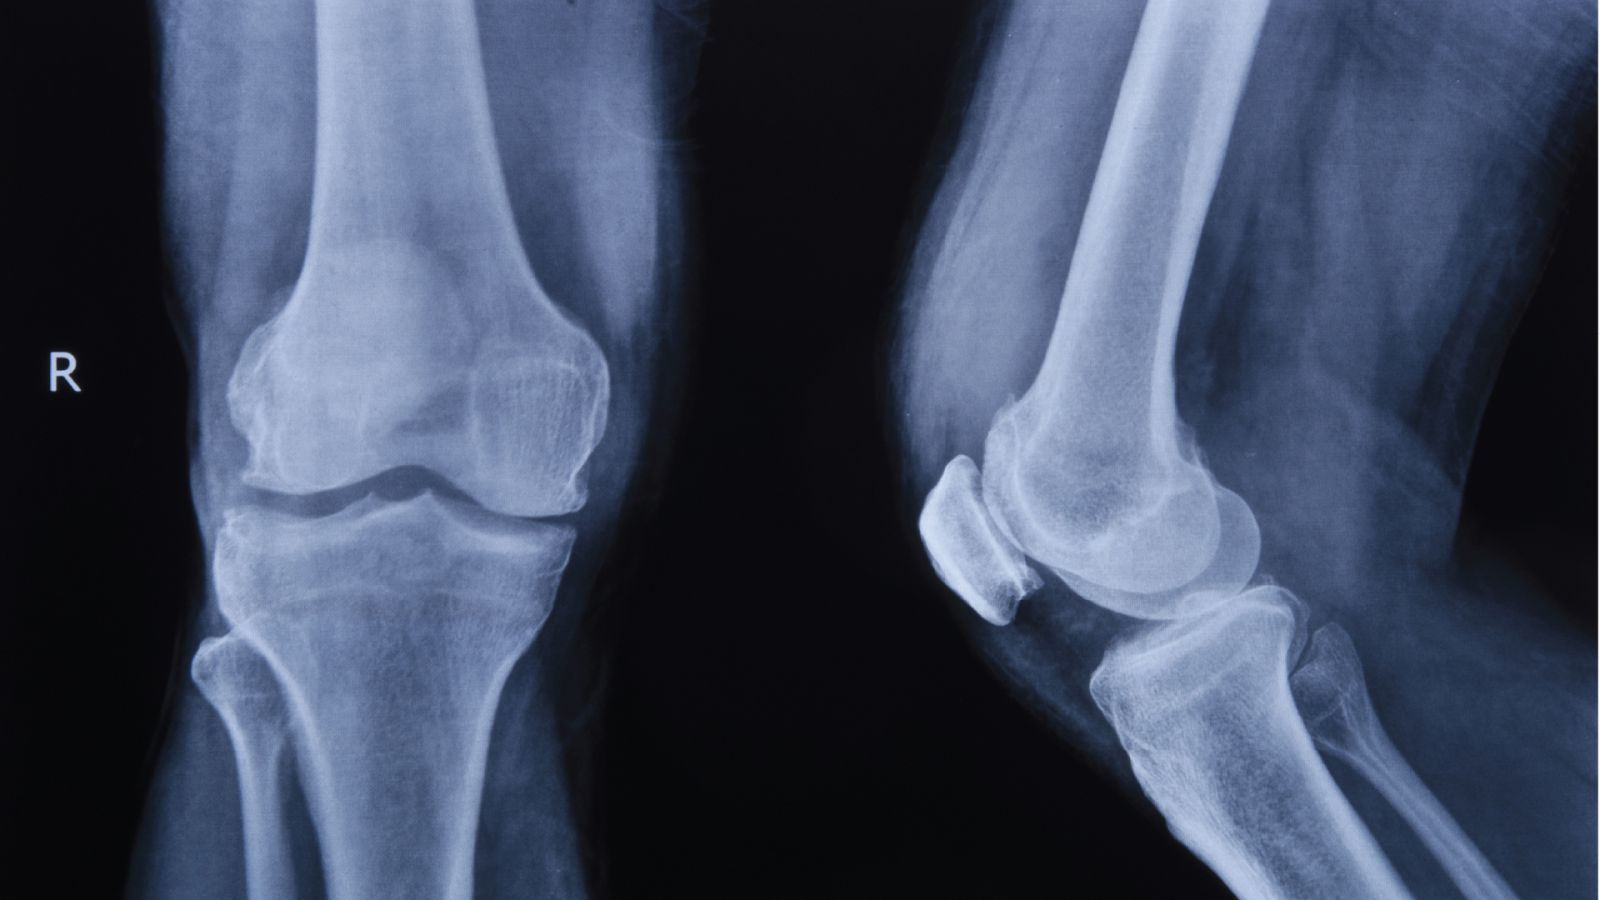

รศ.พล.อ.ท.นพ.จำรูญเกียรติ ลีลเศรษฐพร แพทย์เฉพาะทางกระดูกและข้อ จากโรงพยาบาลเอส เฉพาะทางกระดูกสันหลังและข้อ (S Spine and Joint Hospital) อธิบายว่า ข้อเข่าเป็นข้อต่อขนาดใหญ่ที่ต้องรับน้ำหนักของร่างกายตลอดเวลา ภายในข้อเข่าประกอบด้วยกระดูกอ่อน เอ็น กล้ามเนื้อ และกระดูกชิ้นสำคัญที่เรียกว่า “ลูกสะบ้า” (Patella) ซึ่งอยู่ด้านหน้าของข้อเข่า มีหน้าที่ช่วยเพิ่มแรงให้กล้ามเนื้อหน้าขาในการเหยียดเข่า และช่วยให้การเคลื่อนไหวของข้อเข่าเป็นไปอย่างราบรื่น

เมื่อเกิดภาวะข้อเข่าเสื่อม กระดูกอ่อนที่ทำหน้าที่รองรับแรงกระแทกจะค่อยๆ สึกหรอ โดยเฉพาะบริเวณใต้ลูกสะบ้าที่ต้องรับแรงกดและแรงเสียดสีสูง ส่งผลให้เกิดอาการปวดเข่าด้านหน้า มักปวดชัดเจนเวลาขึ้นลงบันได ลุกนั่ง หรือใช้งานข้อเข่าเป็นเวลานาน